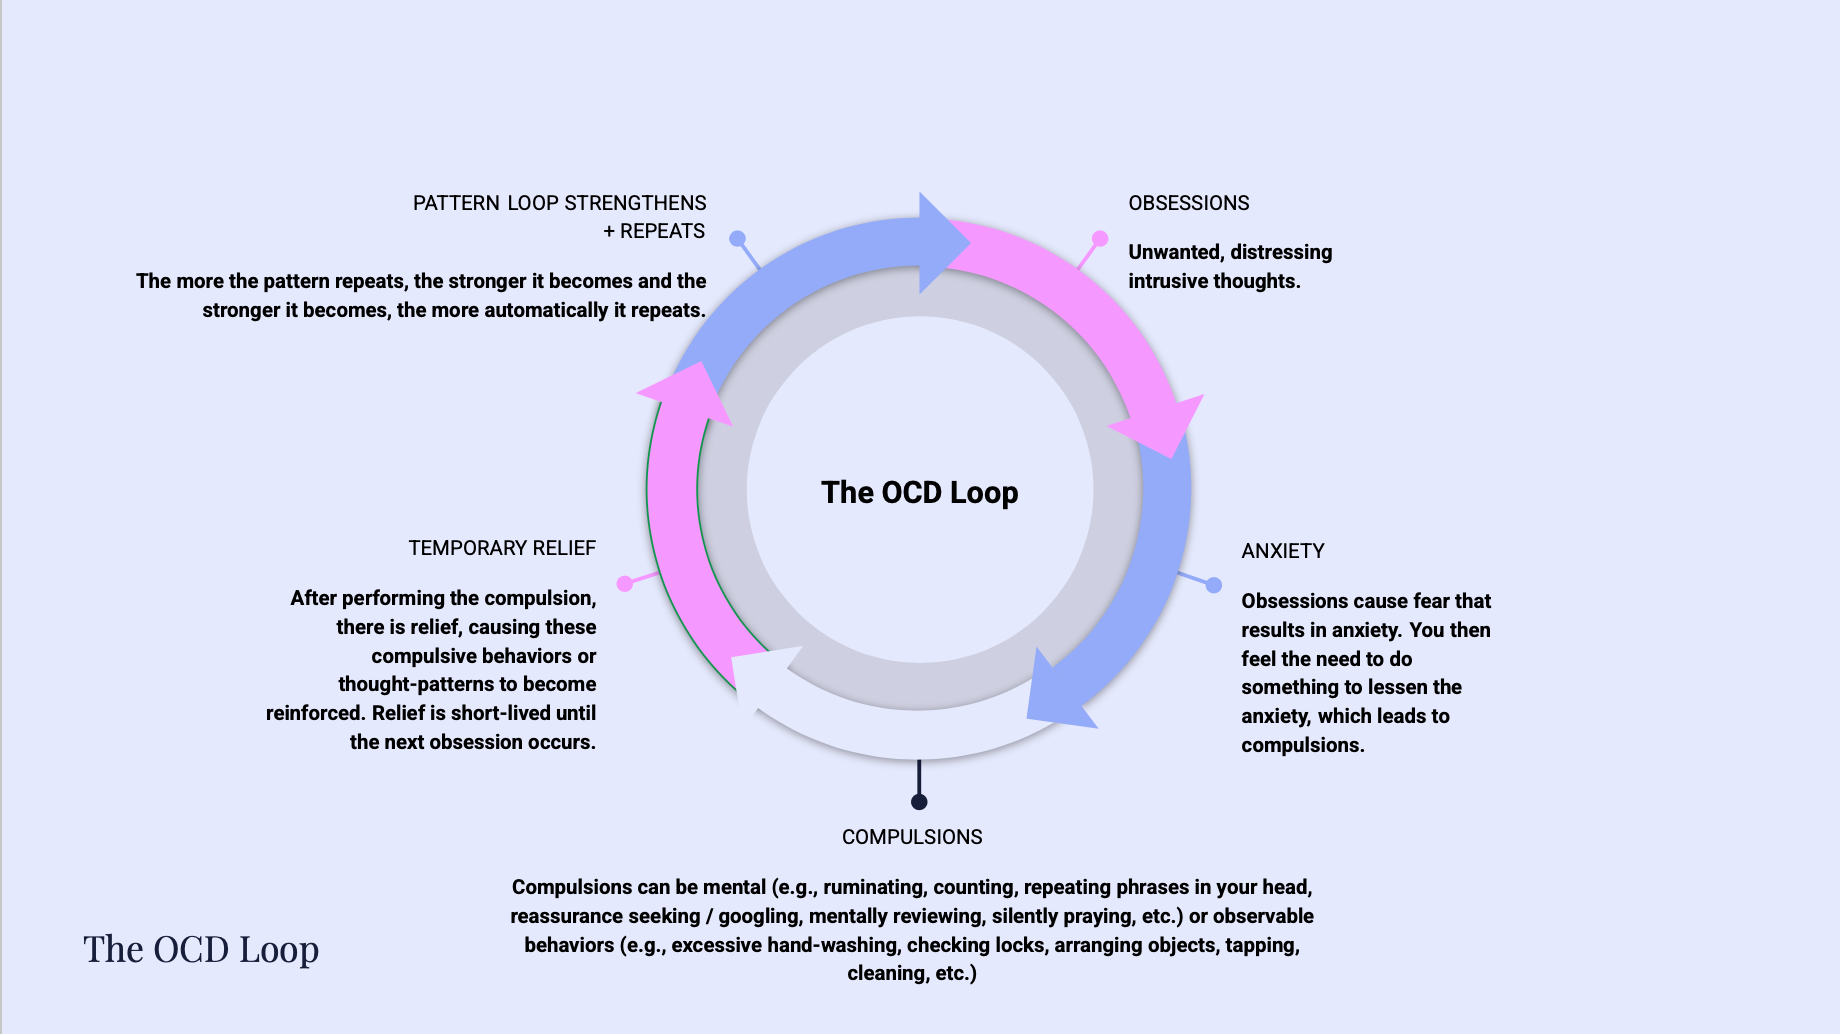

Thoughts vs. Thinking in OCD: The Distinction that Changes Everything

In postpartum OCD, intrusive thoughts aren’t the problem—thinking about them is. Understanding the difference between a thought and thinking, and recognizing thinking (i.e., rumination) as a compulsion, changes everything about recovery.

What is postpartum OCD? (And Why It’s Not What You Think)

Postpartum OCD (perinatal OCD) is more common than most people realize and more misunderstood. Learn what it actually looks like, why it’s so often missed, and what helps resolve it.